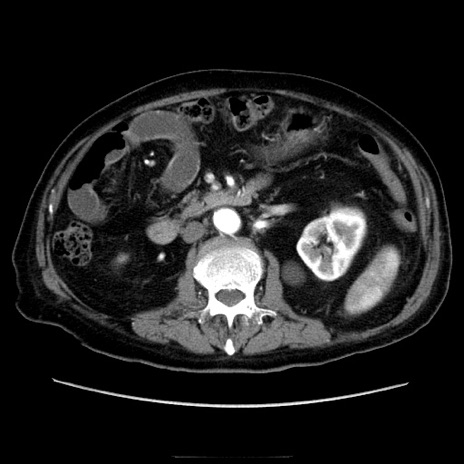

症例21(横断像)

冠状断像

【症例】70歳代男性

【主訴】腹痛

【現病歴】肝硬変・肝細胞癌にてかかりつけの方。約9時間前に食後より腹痛出現。症状が徐々に増悪し、嘔吐出現したため来院。

【既往歴】肝硬変、肝細胞癌(RFA、TACE後)

【身体所見】意識清明、表情苦悶様、BT 36℃、BP 129/78mmHg、P 88bpm、SpO2 97%(RA)、右上腹部から心窩部にかけて圧痛あり、反跳痛なし、筋性防御あり。

【データ】WBC 5800、CRP 0.16